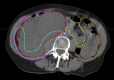

Purpose: To conduct phase 1 and 2 trials with photon intensity modulated radiation therapy and intensity modulated proton therapy (IMPT) arms to selectively escalate the retroperitoneal sarcoma preoperative radiation dose to tumor volume (clinical target volume [CTV] 2) that is judged to be at a high risk for positive margins and aim to reduce local recurrence. We report on the IMPT study arm in phase 1.

Methods and materials: Patients aged ≥18 years with primary or locally recurrent retroperitoneal sarcoma were treated with preoperative IMPT, 50.4 GyRBE in 28 fractions, to CTV1 (gross tumor volume and adjacent tissues at risk of subclinical disease) with a simultaneous integrated boost to CTV2 to doses of 60.2, 61.6, and 63.0 GyRBE in 28 fractions of 2.15, 2.20, and 2.25 GyRBE, respectively. The primary objective of the phase 1 study was to determine the maximum tolerated dose to CTV2, which will be further tested in the phase 2 study.